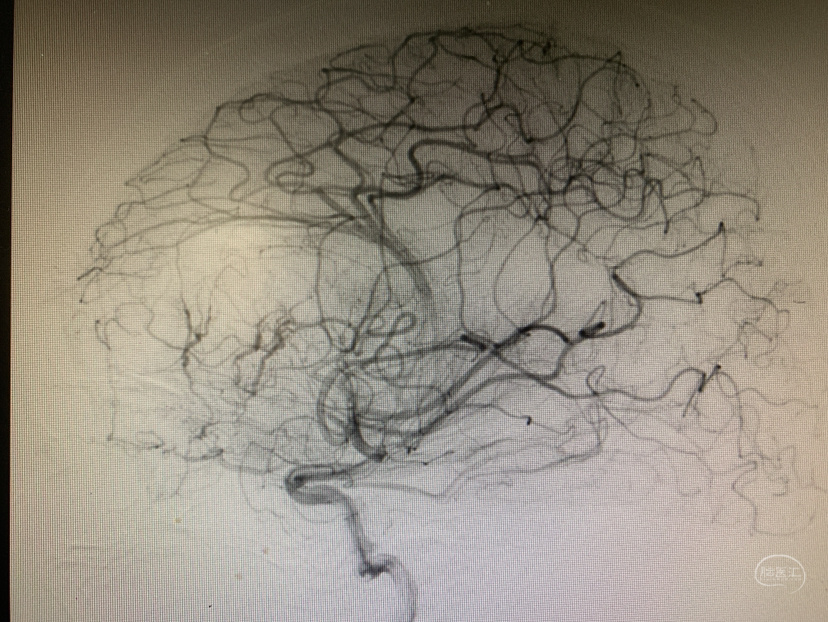

术前造影

神志昏迷双瞳散大对光反射迟钝入院,入院后甘露醇脱水加地米静滴后患者神经功能有改善,能摸索定位,瞳孔反射改善。考虑占位大直接切除可能出血多,拟术前栓塞处理,但造影发现栓塞不易风险高后放弃栓塞。